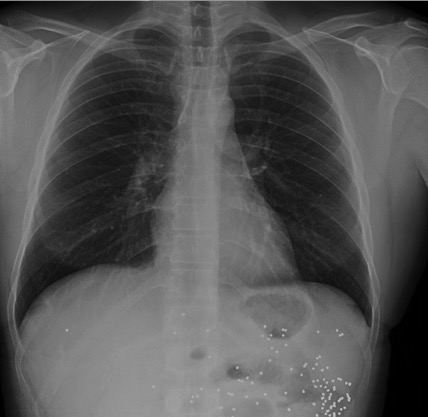

Empecemos, ¿qué ves?

- Comprobar que la placa está bien centrada e inspirada (6 arcos costales anteriores ó 9 posteriores).

- Abdomen y Diafragma

- Partes blandas y estructura ósea.

- Mediastino con silueta cardiaca.

- Parénquimas pulmonares (por separado)

- Comparar un pulmón con otro.

Seguir esta sistemática, dejando el pulmón para el final no nos olvidaremos de lo más importante.

Regla: Acaso Tiene Mucha Patología Pulmonar (Abdomen, Tejidos blandos y hueso, Mediastino, Pulmón por separado, Pulmón bilateral)

Nota: ¡¡¡No olvidar la placa lateral!!! La regla a seguir es la misma. Leer abdomen y diafragma, examinar parte posterior, tejidos blandos y subir por la columna; tráquea y descender por mediastino. Finalmente pulmones.

Solución: Es un estudio Normal. Silueta cardiomediastínica y parénquimas pulmonares sin alteraciones significativas.